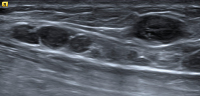

Abbildung 2: Fehlender Hilus. Dieser Lymphknoten weist keinen Hilus auf, alle anderen Kriterien sind jedoch erfüllt. Tumorzellen destruieren die reguläre Architektur des Lymphknotens und führen so zu einer Obliteration der Hilusstruktur. „Diffuse large B-cell lymphoma“ (DLBCL).